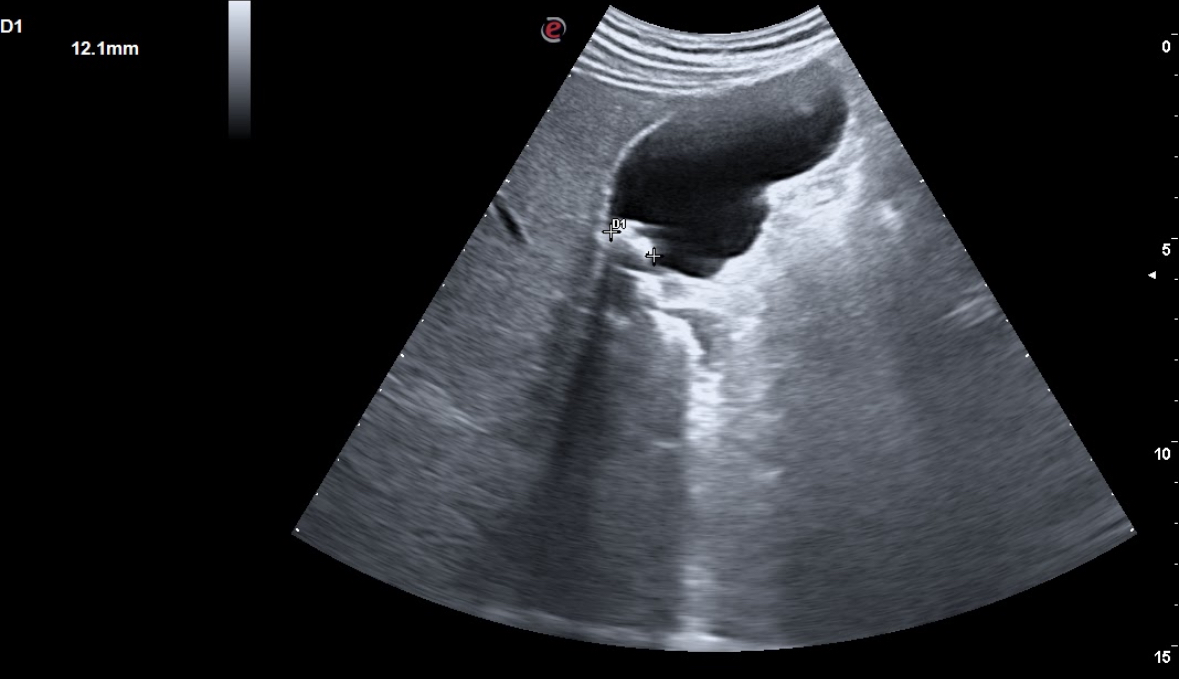

En la radiografía solicitada se aprecia una zona hiperdensa en zona de vesícula, por lo cual realizamos ecografía clínica abdominal en la que se aprecia hígado con ligera hiperecogenicidad difusa homogénea, con tamaño normal, vesícula replecionada con 3-4 imágenes hiperecoicas con sombra acústica posterior, la mayor de 1,2 cm, con una pared de 0,2 mm. Páncreas no visible en ecografía por gas. Vía urinaria normal.